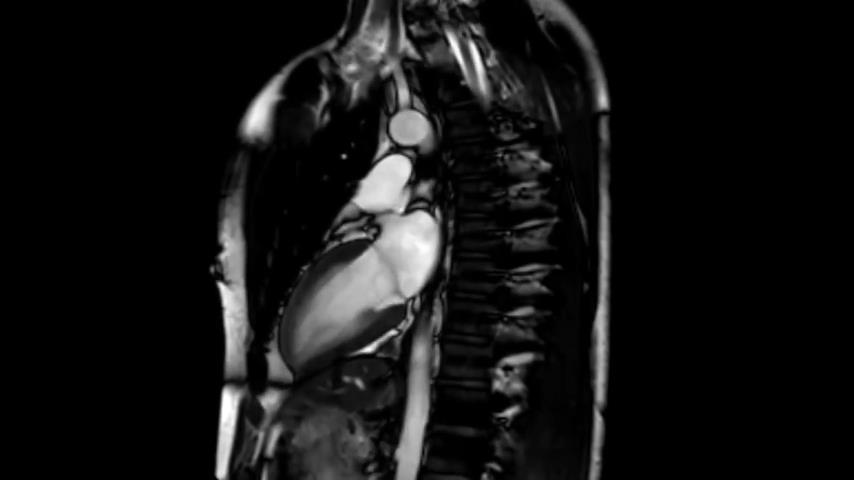

Sehen Sie sich ein pulsierendes Herz an, das von einem hochauflösenden MRT-Scanner aufgezeichnet wurde. Das Video wurde aufgenommen, während der Freiwillige den Atem anhielt, damit die Lunge unbeweglich bleibt.